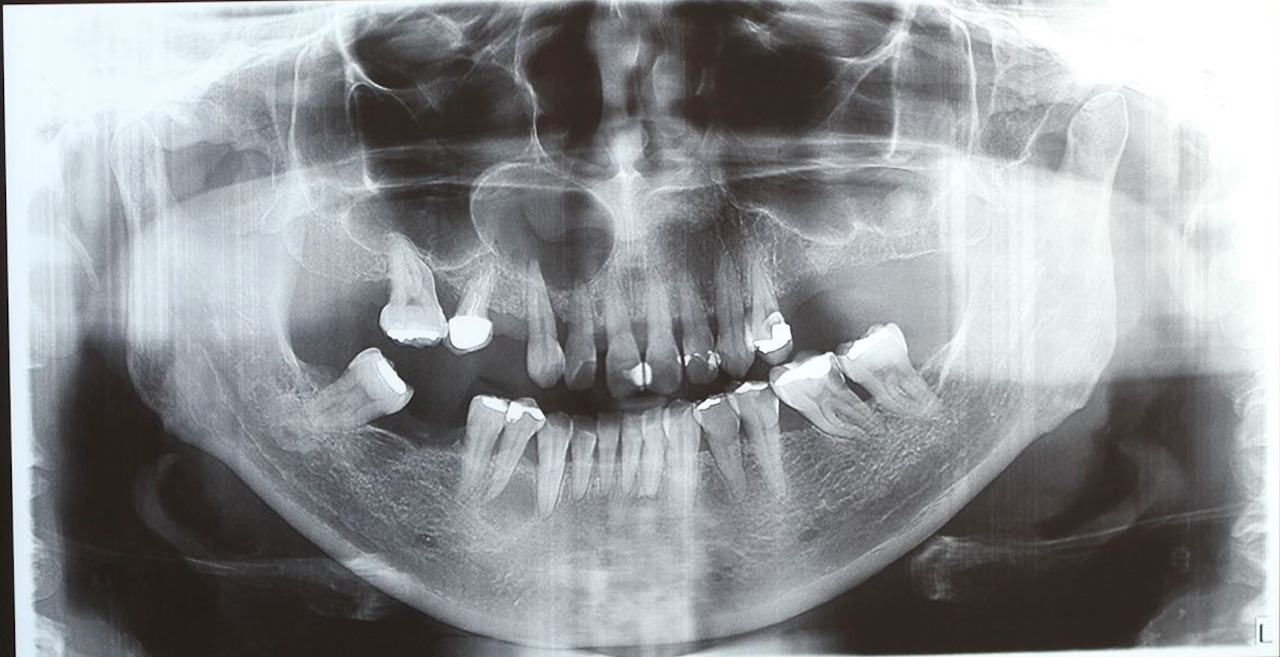

Clinically there was no phlogistic signs and ortopantographics revealed an apical radiolucency with a well-circumscribed sclerotic border in the apical region of the right canine and right maxillary (Figure 1).

Figure 1: Initial panoramic radiography. View Figure 1